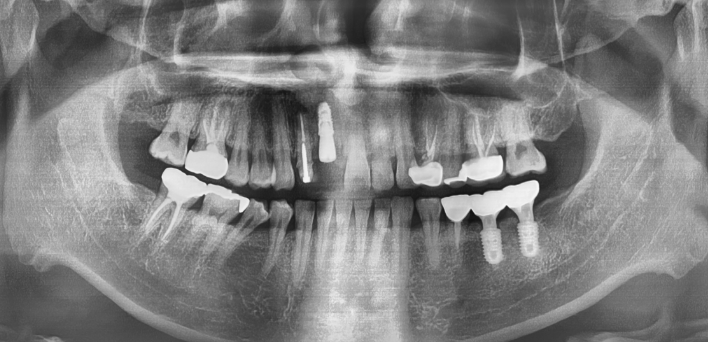

임플란트 : 손 ** 님 (50대)

Before Before

2020.02.30

After After

※ 더서울치과의원은 의료법을 준수하며 위 케이스는 실제 환자의 동의를 얻은 사례로 치료 전, 후가 동일한 환경에서 촬영되었습니다.

환자 케이스에 따라 부작용이 발생할 수 있습니다. 이 부분은 의료진의 충분한 상담과 체크를 통해 예방하고 줄일 수 있습니다.

[임플란트 부작용] 수술 후 관리가 소홀할 경우 출혈, 주위염 등의 부작용이 발생할 수 있어 구강 위생을 철저히 유지하고, 정기적인 검진을 통해 상태를 점검하는 것이 중요합니다.

환자 특징

환자 특징01무치악 상태

환자 특징02수년간 무치악으로 지내심

임플란트가 불가능할것이라

생각하고 내원

위, 아래 6개씩 식립

디지털 풀아치 임플란트